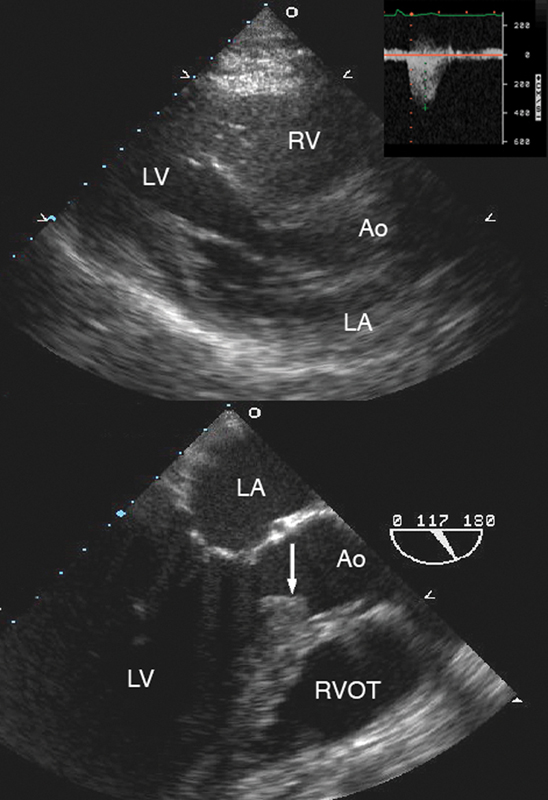

فحوصات تشخيصية لبعض امراض القلب والشرايين التاجية